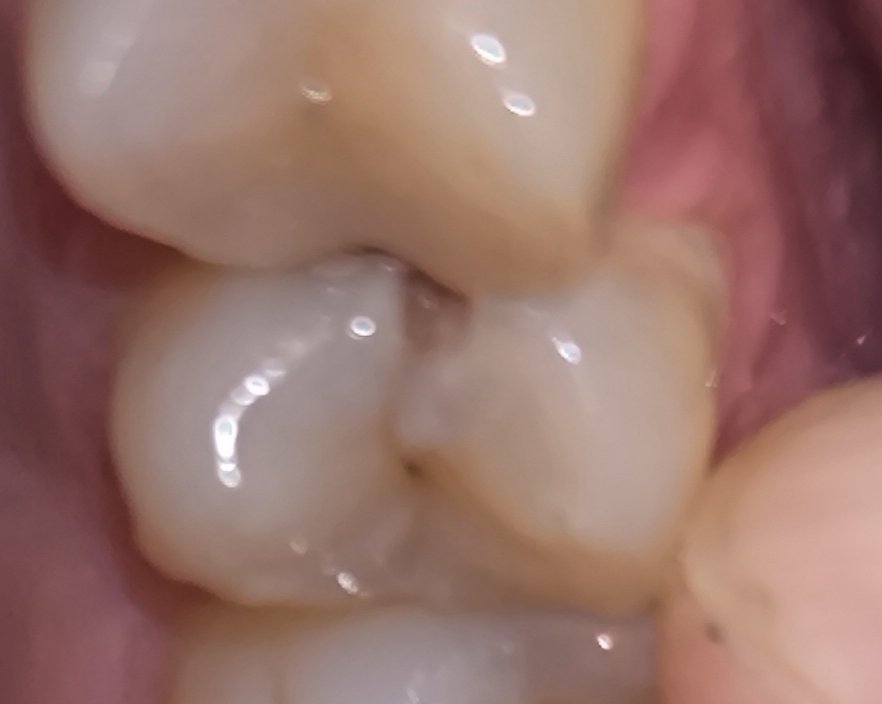

1000070961.jpg 180Кб, 882x704

882x704

Зуб пятерка. Возможно такое вылечить, анонче? Отклолся как то, вообще не болит.